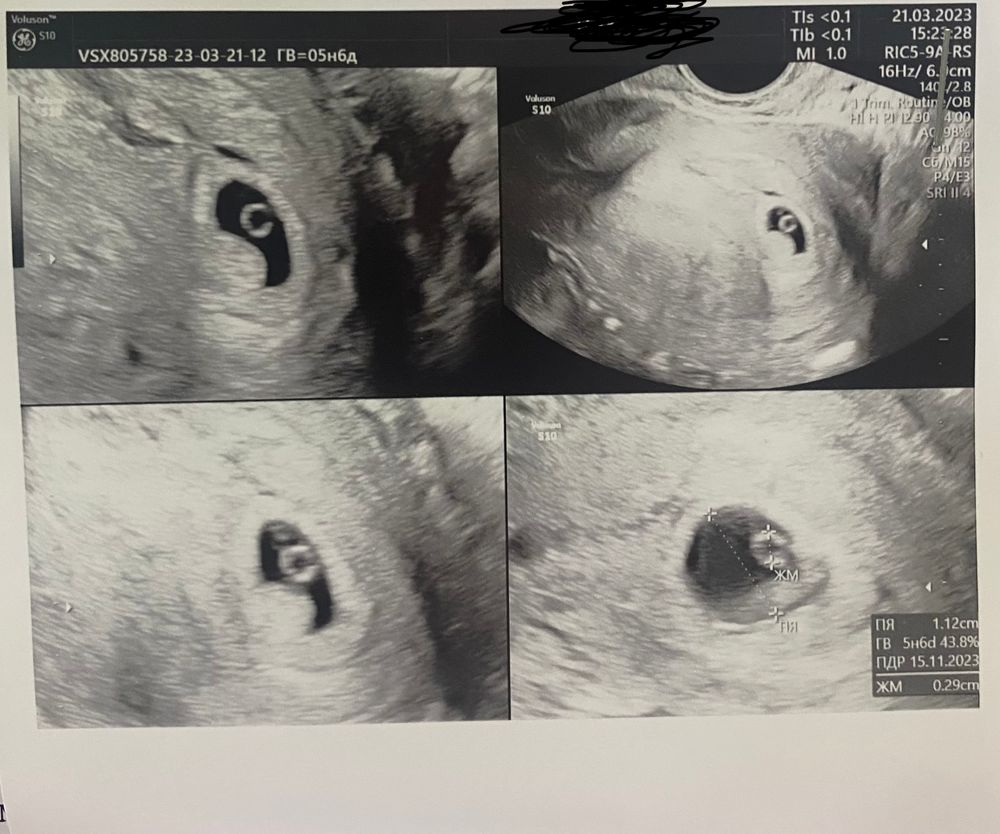

Плодное яйцо неправильной формы

Изображение Вот моя бусинка. В заключении было написано тонус, угроза прерывания. Но я почему-то была уверена, что всё хорошо. Говорят, при УЗИ может быть тонус

В 5 недель было деформировано пя, но был тонус. Как только он прошёл, то и пя стало правильной формы. Родила сына в срок.